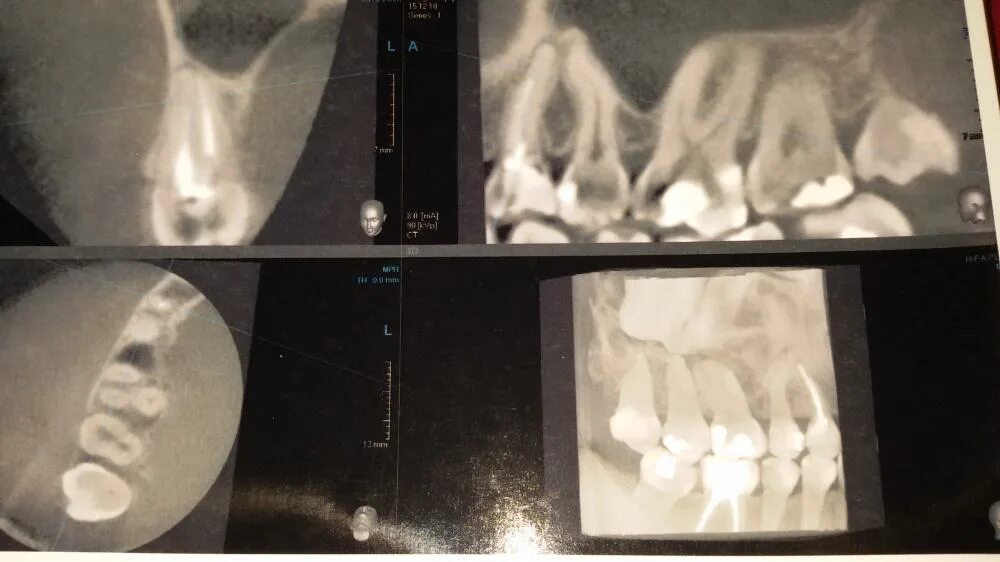

Зубы холодное горячее